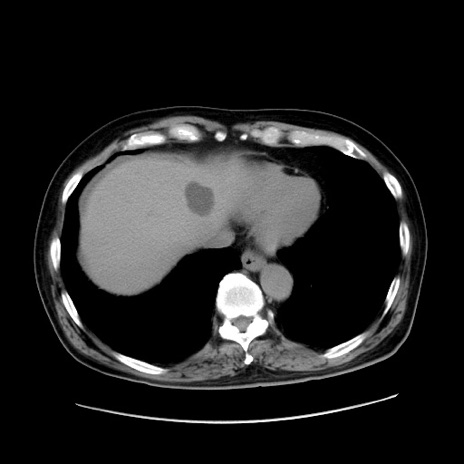

症例30(横断像)

【症例】80歳代男性

【主訴】臍周囲痛

【現病歴】約6時間前から臍下部痛が出現。次第に腹部膨隆・背部痛も生じてきたため来院。背部痛の場所は変化しない。

【身体所見】意識清明、BT 36.3℃、BP  131/87mmHg、P 87bpm、SpO2 100%(RA)、臍周囲自発痛・圧痛あり、反跳痛なし、自発痛部位に一致して板状硬あり、腹部膨隆、腸雑音減弱、CVA tenderness両側陰性。

【データ】WBC 19600、CRP 0.33